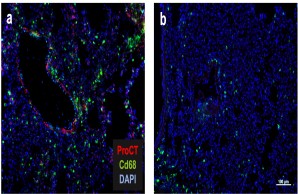

Fig.: Interaction of bone cells with immune cells after osteoanabolic teriparatide therapy. (a) Teriparatide induces procalcitonin (ProCT) expression in osteoblasts, which impairs the recruitment of osteoclast precursors (i.e., monocytes and macrophages) to the bone surface, thereby inhibiting bone resorption. (b) Circulating calcitonin (CT) impairs the osteoanabolic effect of iPTH based on tonic inhibition of bone formation, presumably via osteoclasts. Modified from Baranowsky et al, Bone Research 2022.

Fig.: The role of procalcitonin in post-traumatic sepsis. The sepsis biomarker procalcitonin (ProCT) is not only used to diagnose bacterial sepsis, but also functions as a pathophysiological mediator in this disease. ProCT enhances the generalized inflammatory response in sepsis, leading to tissue injury, shown here in immunofluorescence of macrophages (Cd68) in lung preparations (a). If procalcitonin is blocked during sepsis, the inflammatory response and tissue damage are much less pronounced (b). Modified from Baranowsky et al, Critical Care Medicine 2021.